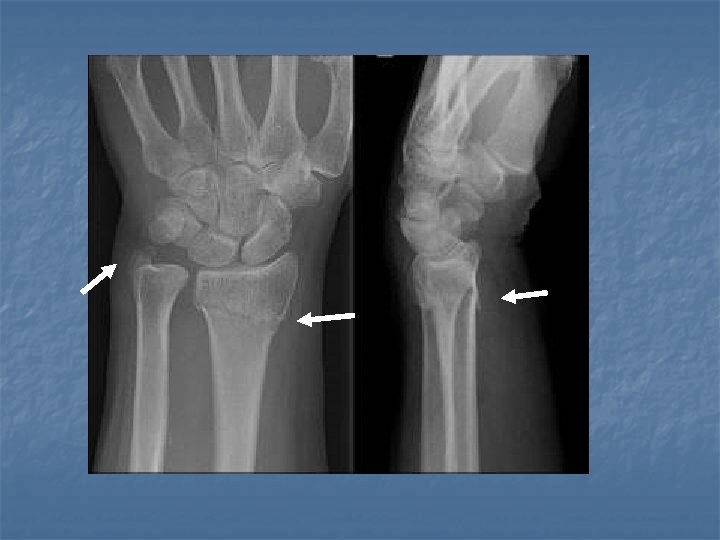

Smith Fracture n n n Fracture of the distal radius with volar displacement and angulation of the distal fragment Results from a fall on the back of the hand or a direct blow to the dorsum of the hand. Often referred to as a reverse Colles fracture.

Smith Fracture